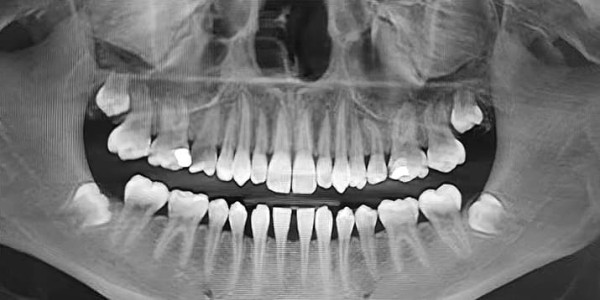

— Вот еще один пациент (см. рис. 3) с верхними «восьмерками», залегающими очень близко к верхнечелюстным пазухам, что несет большие риски при удалении. Иногда на удаление направляют пациентов с начинающими прорезываться «восьмерками», при этом показания к удалению отсутствуют, т. е. третьи моляры не препятствуют дистализации (см. рис. 4).

Рисунок 4. Ортопантомограмма пациентки 15 лет. Показаний к удалению «восьмерок» нет.